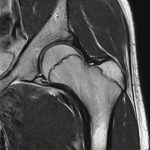

Hình ảnh giải phẫu MRI khớp háng.

Axial / Coronal / Sagittal.